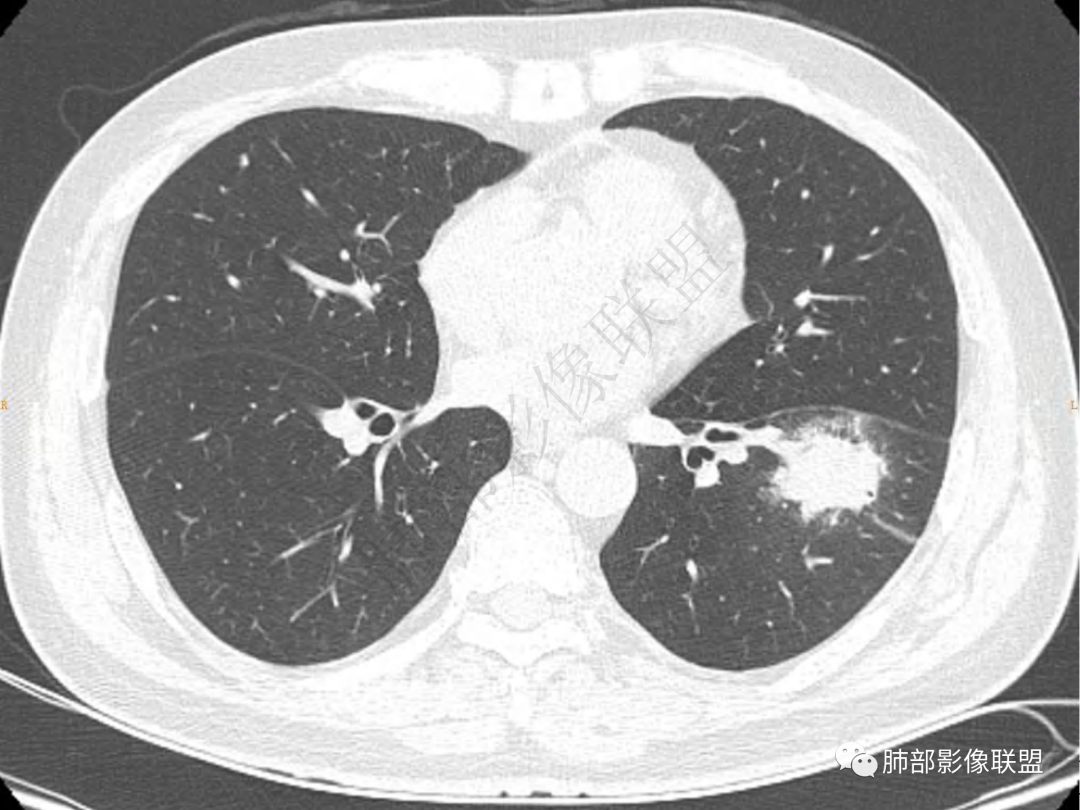

4.实性部分不均匀环形强化并显示一小范围低密度坏死区或空洞。较之肺窗,整体纵隔窗范围较小,提示病灶并不十分密实。抑或为不同时段图像。

5.双肺门及纵隔未见增大淋巴结。未见胸腔积液。

1.病灶不够密实,没有典型分叶,收缩乏力等,支气管未见截断等,缺乏一般肿瘤性肿块特征。

2.周围磨玻璃影边界不清缺乏限制,甚至“激惹”到相邻肺叶,也许提示较明显的炎性水肿。